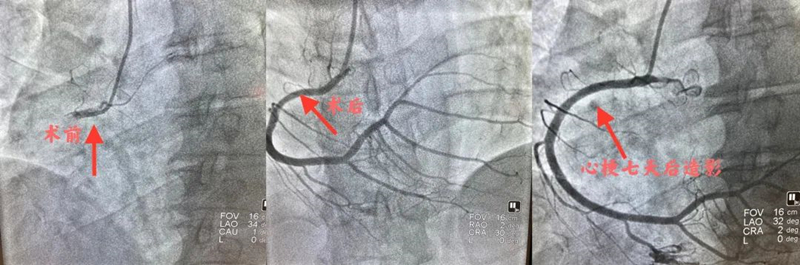

经过术前准备,仅用10分钟就将患者推入了介入中心进行造影检查。造影后,于主任团队发现患者的右冠(右侧冠状动脉)已完全闭塞,于主任立即向家属沟通患者病情,并决定为患者打开闭塞的右冠血管。患者年轻,导丝滑过后球囊扩张,发现大量血栓,经过抽吸血栓、静脉应用药物后患者血流恢复,胸痛立即缓解。于主任向家属表述患者病情为一个严重的血管高凝血栓事件,建议强化抗栓抗板后复查造影,再进一步决定是否需要植入支架。

经过心血管内二科医护团队的精心治疗,七日后,患者复查造影血管恢复良好,无需植入支架。患者家属听到这个结果时双眼热泪盈眶。患者年仅40岁,上有老、下有小,对于家庭的重任他不能倒下,于主任团队对患者精心治疗的同时,还对患者进行了日后心脏康复的指导及心理辅导,次日患者顺利出院。